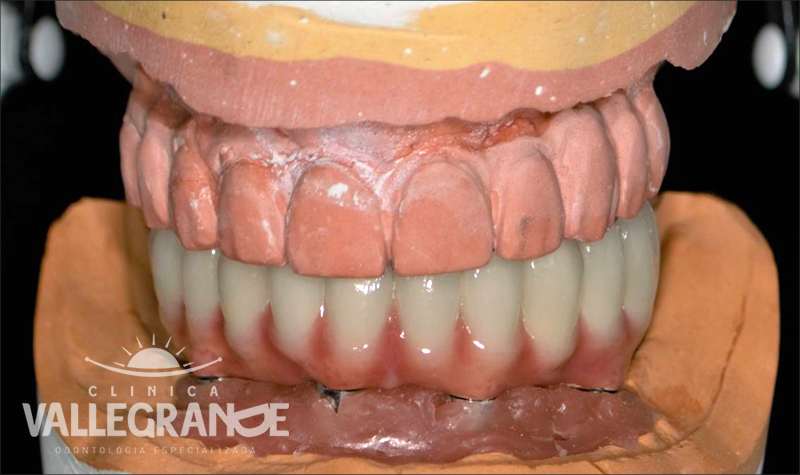

Prótesis híbrida superior de cerámica fija sobre implantes.

Prótesis híbrida superior de cerámica fija sobre implantes